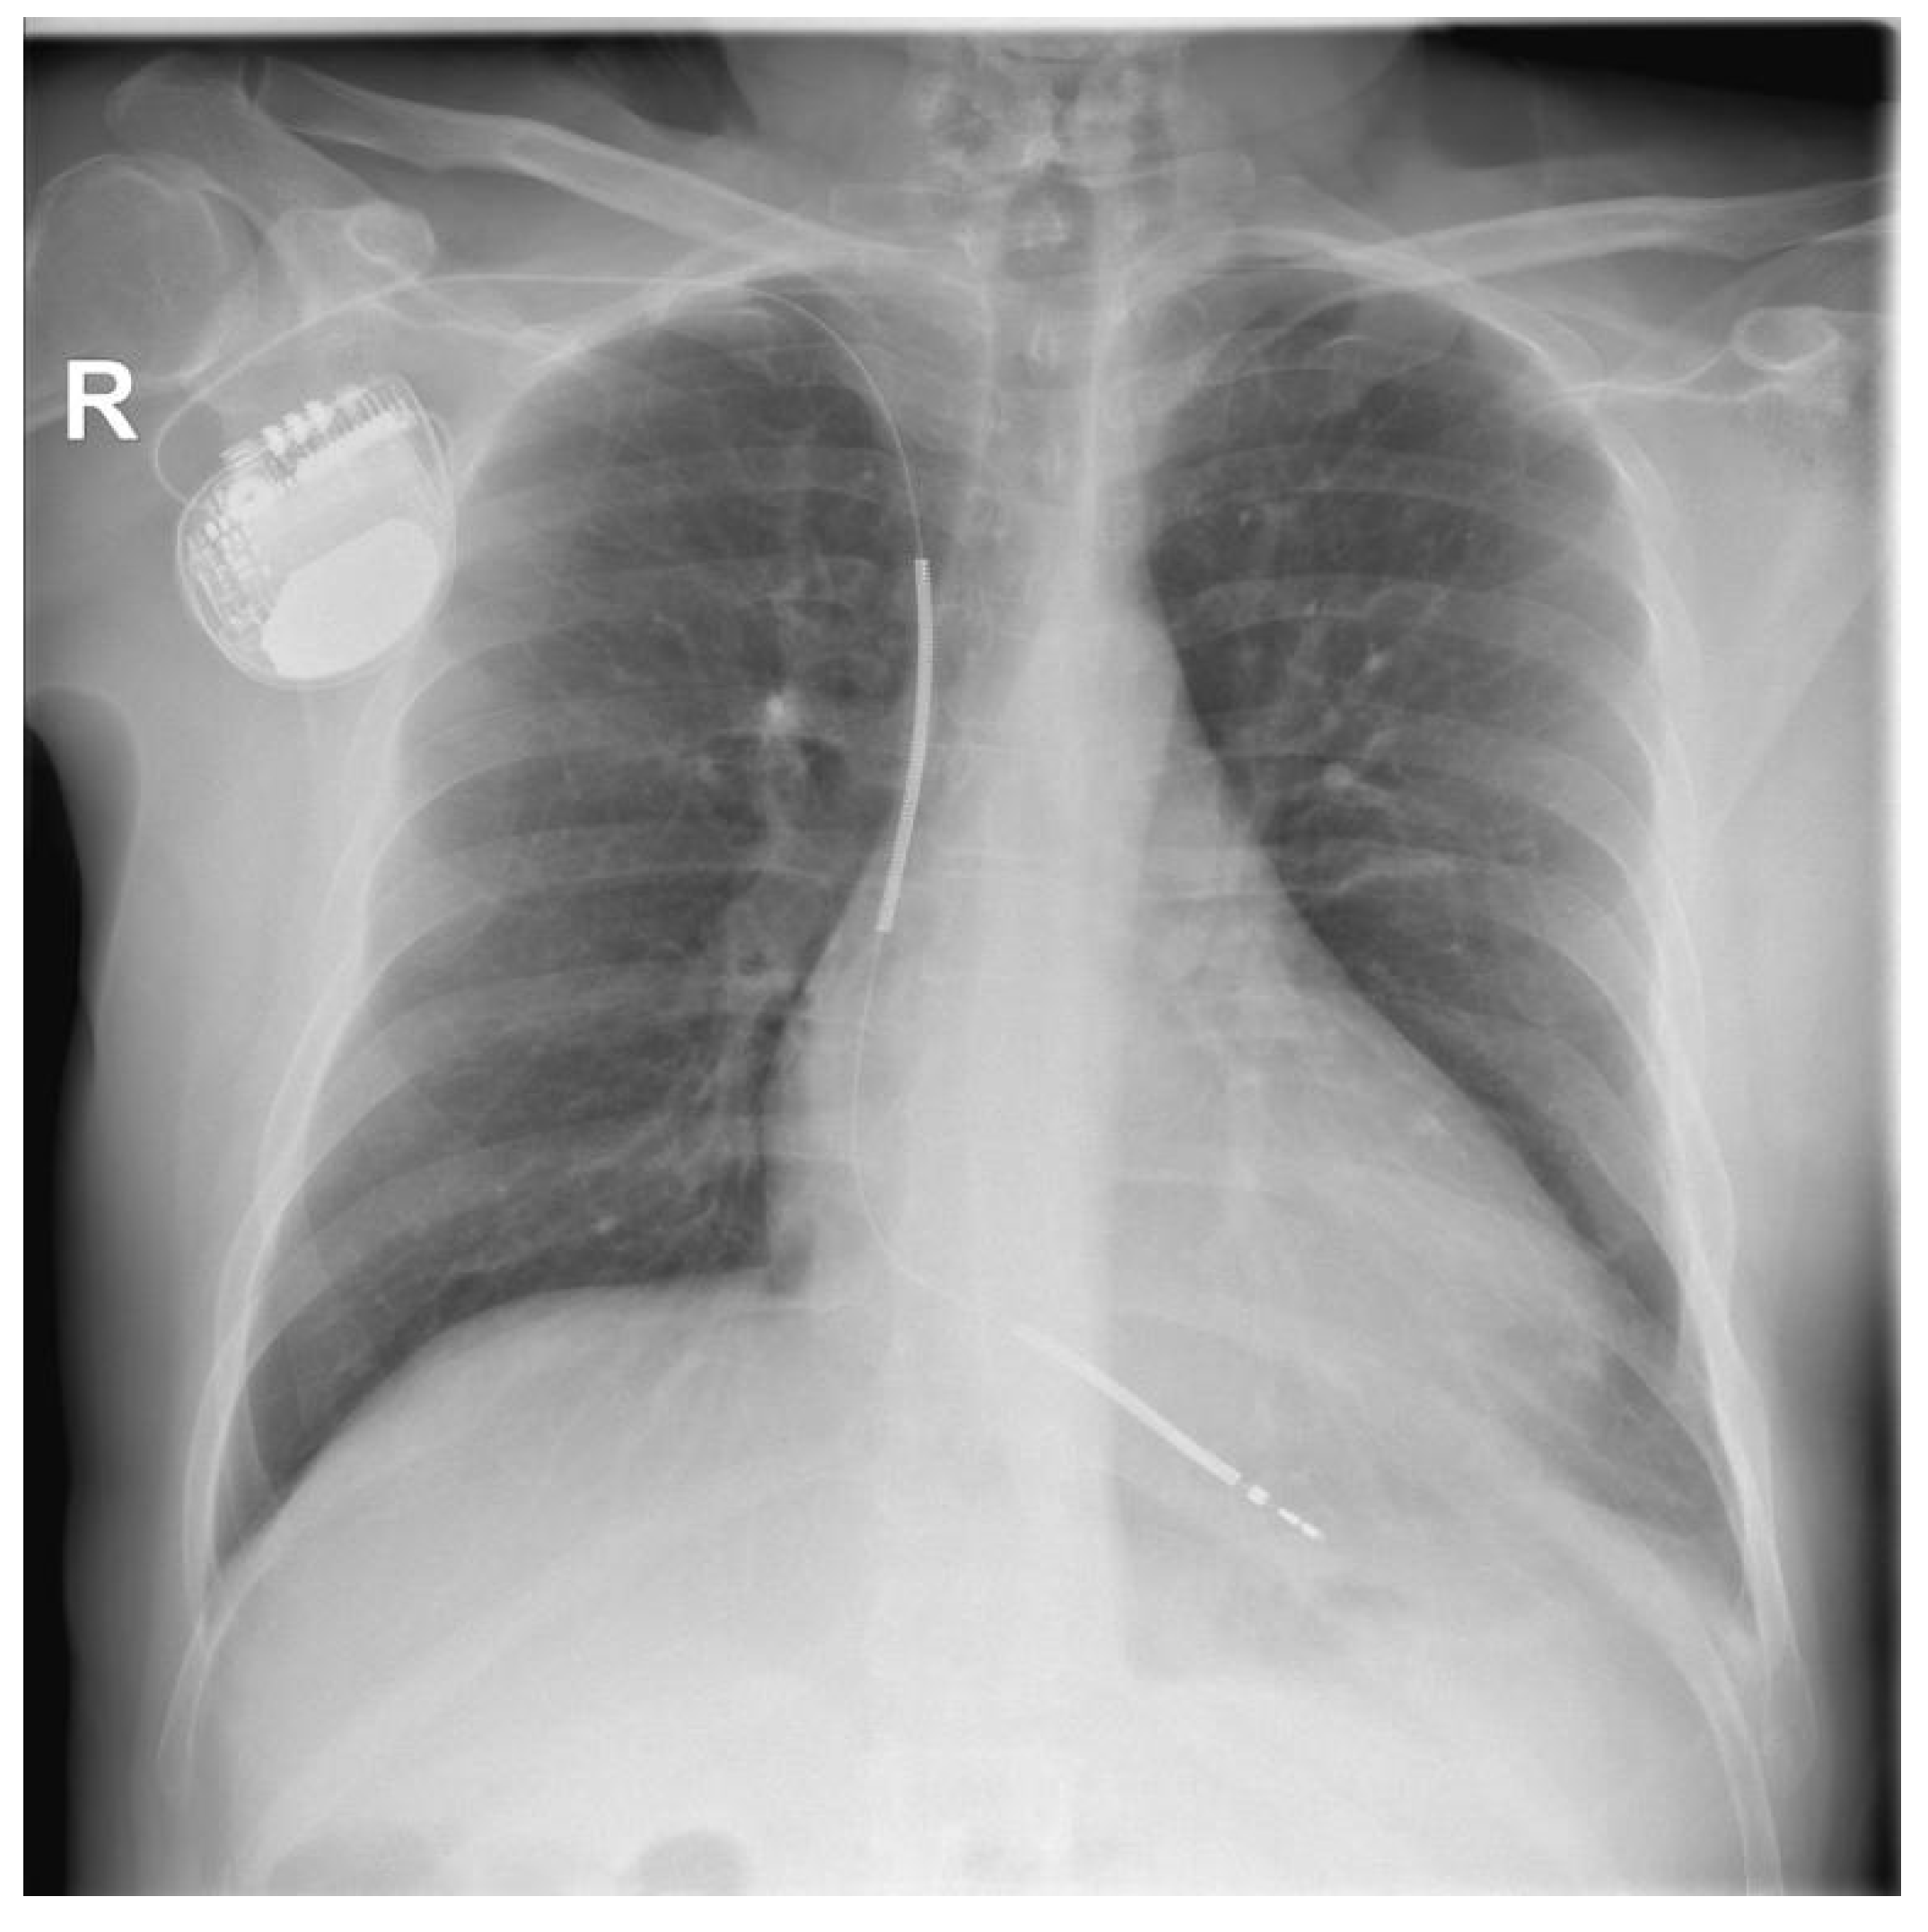

Post-procedural echocardiography revealed no pericardial effusion, no additional tricuspid valve dysfunction, and no lead fragments. The control chest X-ray after the procedure revealed the leads were in normal positions, as shown in Figure 7.

Figure 7. CRT-D system with leads in normal positions: (a) posteroanterior view and (b) left anterior oblique view.